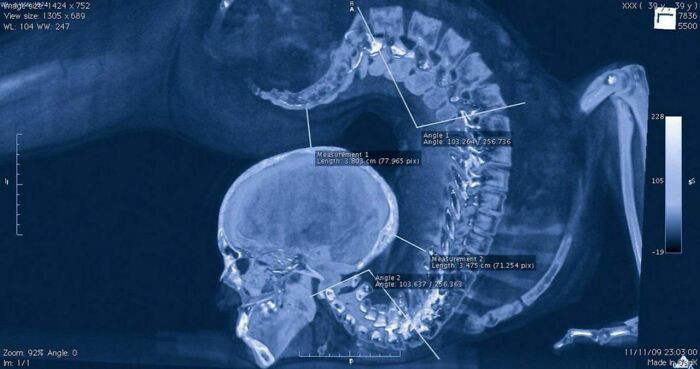

Radiografía de una gimnasta realizando un ejercicio